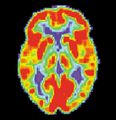

مرض ألزايمر هو مرض تنكسي وقاتل يصيب المخ، حيث تُفقد الاتصالات الخلوية بخلايا المخ. يعتبر مرض ألزايمر من أكثر أنواع الخرف شيوعاً.[2] عالمياً، يصاب بمرض ألزايمر حوالي 1-5% من السكان.[3] تقع النساء بشكل غير متناسب ضحايا لمرض ألزايمر، مع وجود أدلة تشير إلى أن النساء المصابات بمرض ألزايمر يظهرن ضعفاً إدراكياً أكثر حدة مقارنة بالذكور المصابين بالمرض، بالإضافة إلى معدل أسرع من التدهور السلوكي.[4]

مسح PET لمخ غير مصاب - الصورة مقدمة من مركز الإحالة والتوعية بمرض ألزايمر التابع للمعهد الوطني للشيخوخة بالولايات المتحدة.

مسح PET لمخ مصاب بمرض ألزايمر - الصورة مقدمة من مركز الإحالة والتوعية بمرض ألزايمر التابع للمعهد الوطني للشيخوخة بالولايات المتحدة.